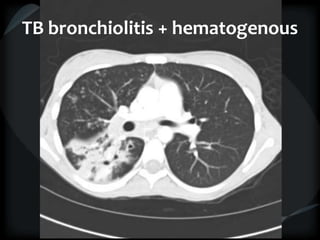

CT features of tuberculosis

 Transbronchial spread – tree-in-bud

 Transbronchial and hematogenous

Tuberculosis – TB spread

Tuberculosis

bronchiolitis + hematogenous

TB bronchiolitis + hematogenous

CT features oftuberculosis  Cavity  Transbronchial spread – tree-in-bud  Transbronchial and hematogenous

TB bronchiolitis +hematogenous